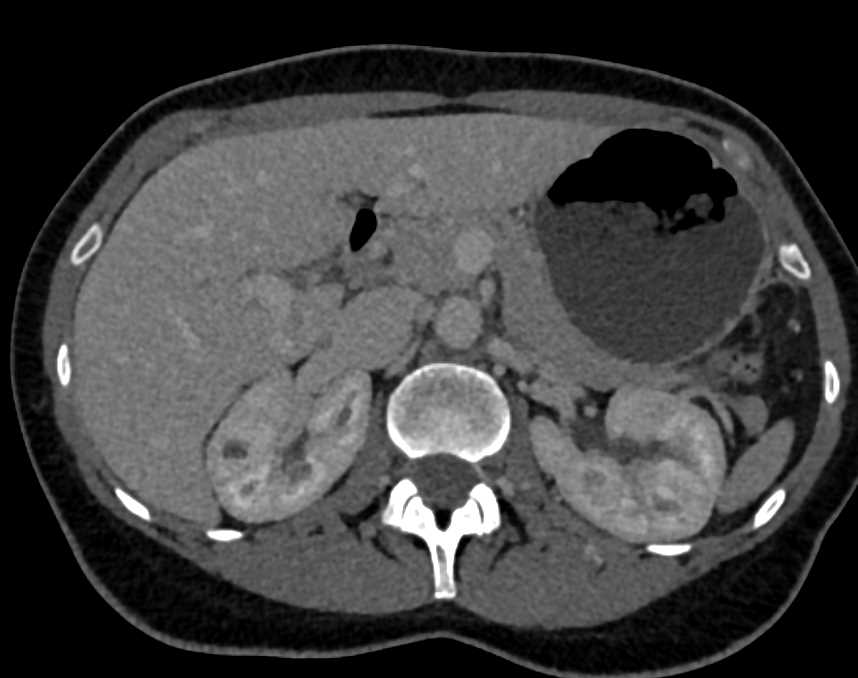

Subtle Incidental Bladder Cancer